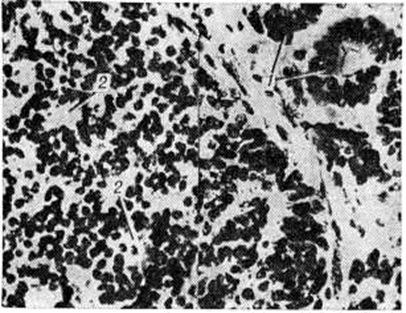

Рис. 3.

Микропрепарат симпатобластомы: среди опухолевых клеток видны истинные (1) и ложные (2) розетки; окраска гематоксилин-эозином; × 450.

Симпатобластома — более дифференцированная опухоль. Она содержит отростчатые нейробласты с крупными телами овальной, вытянутой иди полигональной формы, с пузырьковидным ядром, содержащим глыбки хроматина в виде спиц в колесе. Располагаются клетки плотно, иногда в виде тяжей, колонн, пучков. В ряде случаев встречаются ложные или истинные розетки (рисунок 3), некротические очаги. Разграничить симпатогониомы и симпатобластомы не всегда удаётся: такие опухоли, согласно номенклатуре ВОЗ, обозначают как нейробластомы.